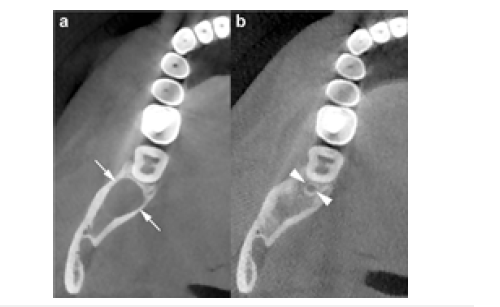

Panoramic (a) and cross-sectional (b) Cone Beam Computed Tomography (CBCT) images show an osteolytic odontogenic lesion in the posterior left mandible and ramus, demonstrating growth primarily along the length of the bone (double-headed arrow) with only minimal expansion of the buccal and lingual cortical plates (curved arrows) (Figure 5a). Mesial displacement of the impacted third molar and inferior displacement of the mandibular canal (arrowheads and dots) are evident. A small, incomplete internal septum (small black arrows), reflecting endosteal scalloping of the cortical plate, is also visible. The wavy arrow indicates the mandibular foramen. Panoramic CBCT imaging with a 20-mm slice thickness (a) shows a mandibular OKC containing a septum (opposing arrows) that appears to divide the lesion into two major loculations. Displacement of adjacent teeth is evident (Figure 5b). However, panoramic (b) and axial (c) CBCT images reconstructed at 0.5-mm and 0.2-mm slice thicknesses, respectively, demonstrate that the septum is actually incomplete (arrows). Perforation of the buccal cortex in the anterior portion of the lesion is also visible (curved arrows).

Figure 5: